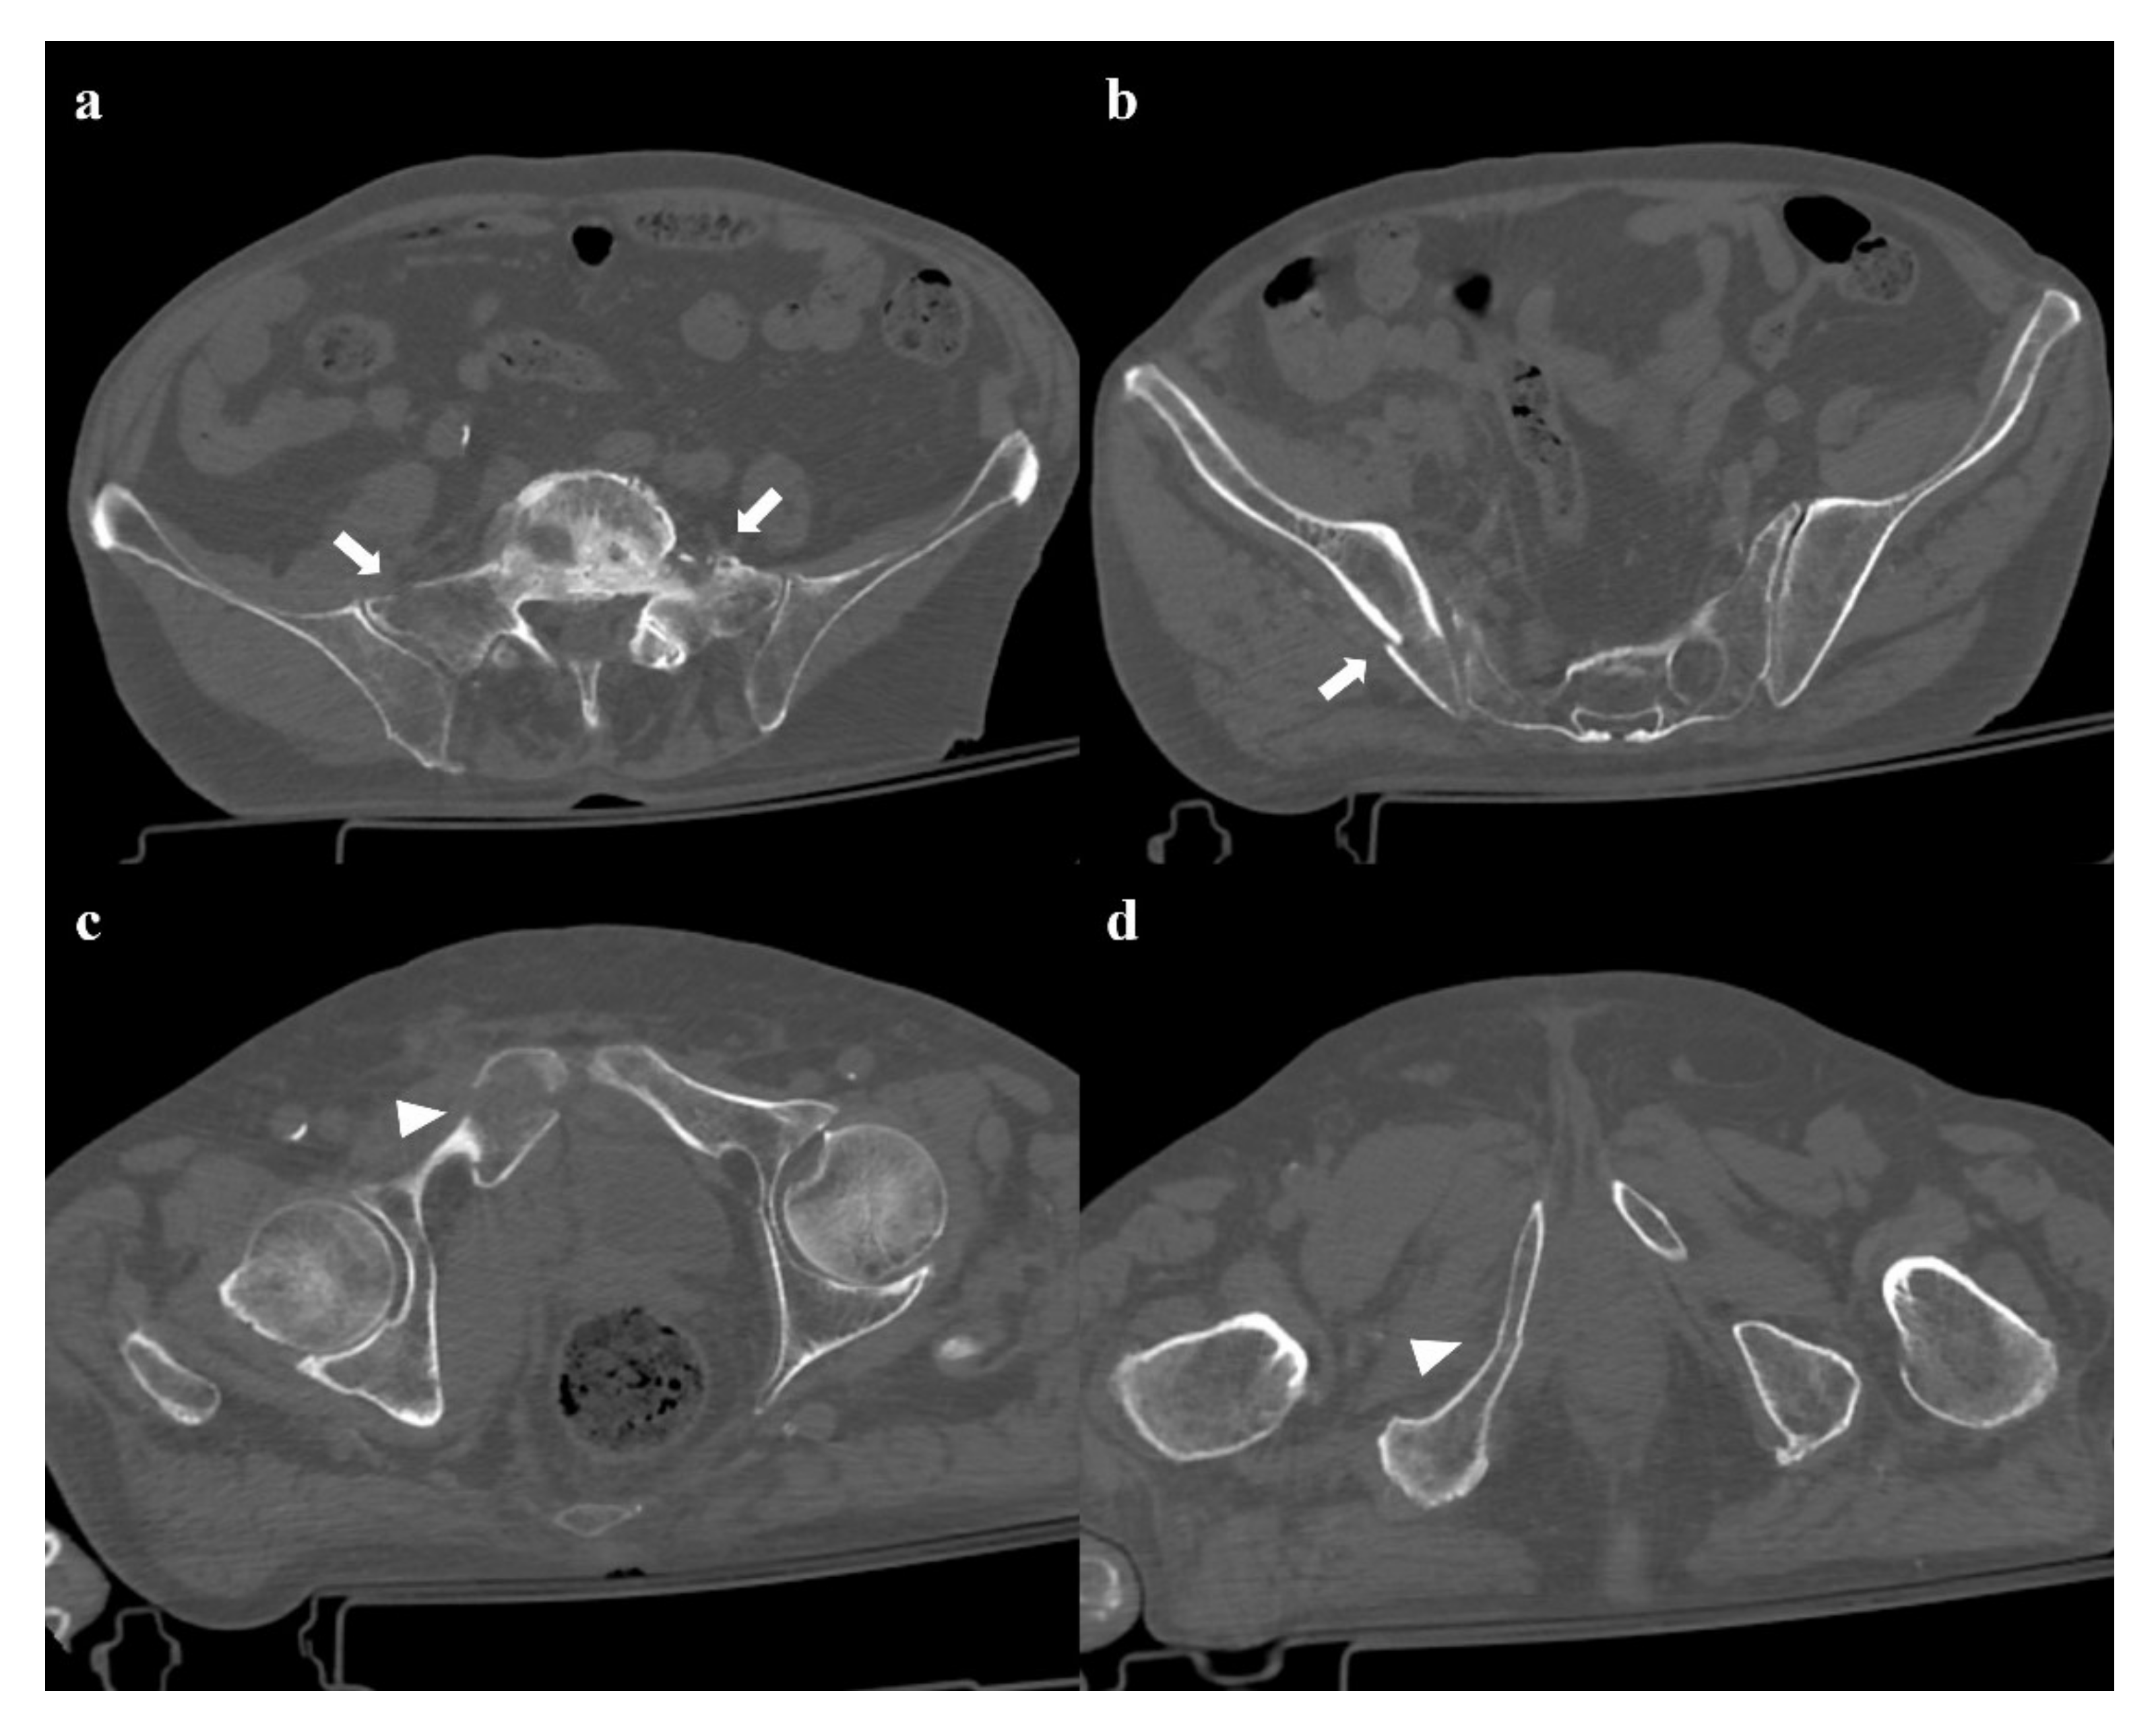

• Grade 3: pubic symphysis diastasis >2.5 cm, possible vertical fracture of the pubic rami, and anterior and posterior sacroiliac joint diastasis (Figure 6). Anterior–posterior compression grade 3 injuries have a multidirectional instability and require a stable internal fixation [3].

Figure 6. Anterior–posterior compression fracture, type 3. Axial CT images (a,b) and three-dimensional volume-rendering CT reconstructions in AP and inlet views (c,d) show a pubic symphysis diastasis of 4.2 cm, anterior and posterior left side sacroiliac joint diastasis, and anterior widening of the right sacroiliac joint.